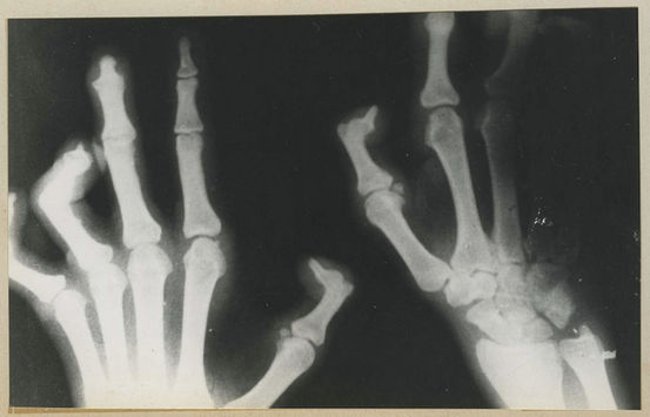

Bệnh phong ("Leprosy" hay còn gọi là bệnh cùi) là một bệnh nhiễm trùng hệ thống mạn tính do trực khuẩn phong gây ra. Bệnh phong có thể gây ra các triệu chứng liệt cơ chân, cơ tay và mất cảm giác trên các vùng da, nhất là ở bàn tay và bàn chân. Tuy nhiên, thực tế hiện nay căn bệnh này ít cực đoan hơn và hoàn toàn có thể điều trị được.

Nguồn ảnh: National Museum of Health and Medicine/Contributed by Major Buker O.S.G. [Office of the Surgeon General]

Thời gian gần đây, bệnh phong còn được gọi là bệnh Hansen, nó do vi khuẩn trực khuẩn phong (Mycobacterium leprae) - vi khuẩn kháng axit không lông không vỏ, không sinh nha bào, có thể nằm riêng rẽ nhưng thường hợp thành bó song song hoặc từng cụm. Căn bệnh này gây tổn thương cho da và tổn hại thần kinh vĩnh viễn, tuy nhiên có một quan niệm sai lầm rằng đó là nguyên nhân gây liệt các bộ phận trên cơ thể người.